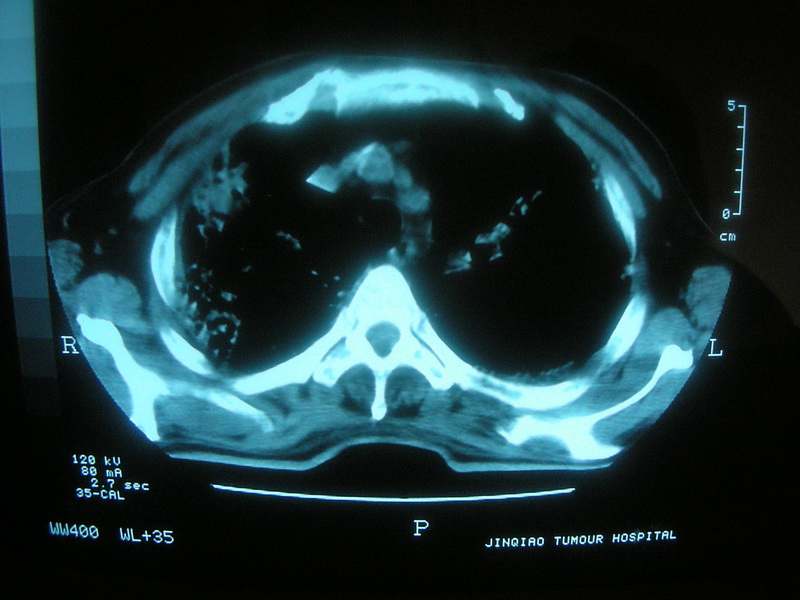

标题: CT11692:男,63岁,糖尿病史15年.抗炎治疗7天,病情 [打印本页]

标题: CT11692:男,63岁,糖尿病史15年.抗炎治疗7天,病情

请老师看看是结核还是炎症?

根据影像表现及临床符合结核感染。

双肺继发性肺结核伴感染!

双肺继发性肺结核伴支气管播散。